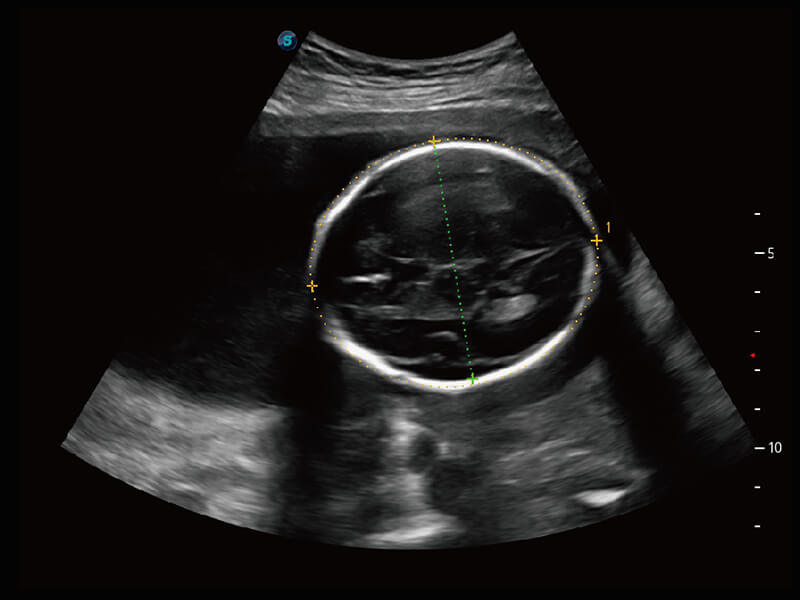

S-Fetus 产科扫查助手

• 缩短

操作时间

• 提升

准确率

• 单次

按键操作